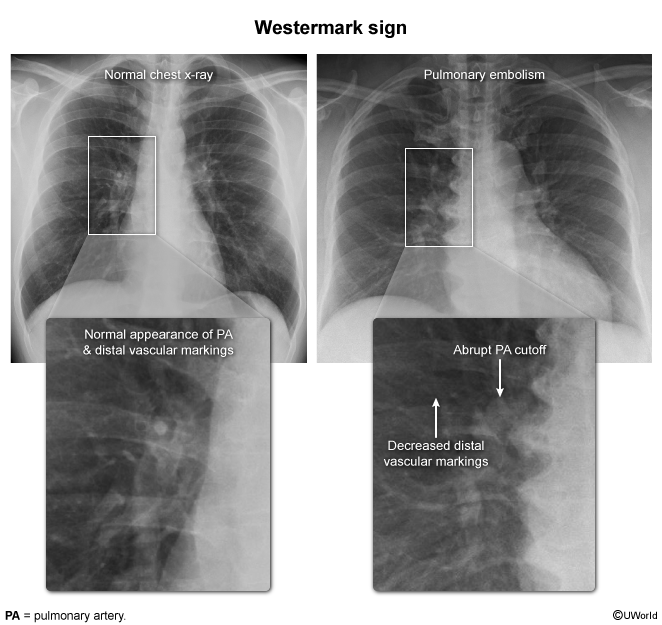

- CXR: Usually normal. Rare signs: Hampton Hump (wedge opacity), Westermark Sign (oligemia).